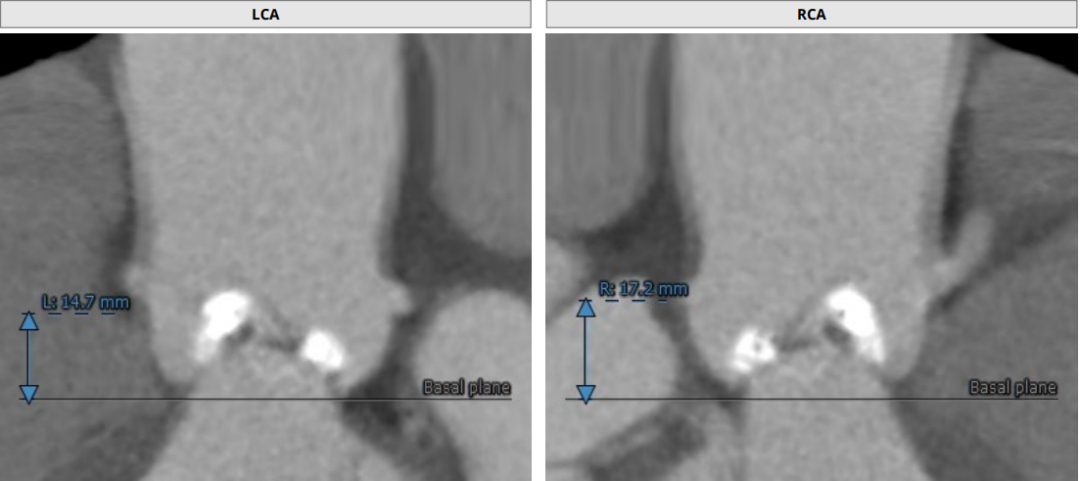

术前CT评估

Annulus Dimensions—27.4mm

LVOT—31.1mm

窦部:28*43.1mm

STJ—39.5mm

升主最宽处:50.5mm

路入分析:右股动脉

患者为Type0型二叶瓣,瓣叶明显增厚,极重度钙化,法式窦结构不大,双冠高度可,初步判断冠脉风险低,升主动脉明显增宽,左室肥大,EF值只有24%,心衰指征明显术中存在循环崩溃的可能;主动脉弓部走行较平缓,推荐右侧股动脉做为主入路。